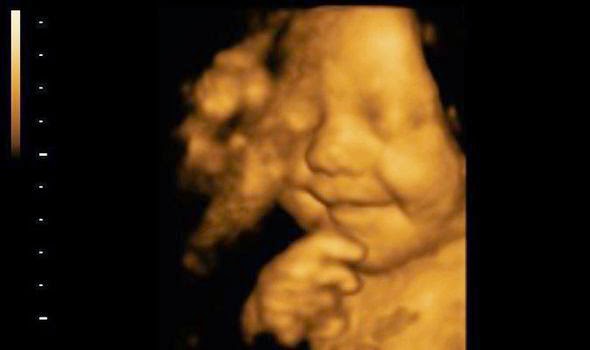

La photo du jour